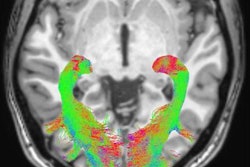

Swiss biopharmaceutical company AC Immune will conduct a clinical trial in the second half of 2018 to evaluate the viability of a new PET tracer for Parkinson's disease.

The study will examine the PET tracer's selectivity for aggregates of alpha-synuclein, a key target in Parkinson's, and thus its capacity to serve as an imaging biomarker for the disease, according to AC Immune. The company is presenting its current research on the topic at the AAT-AD/PDTM 2018 focus meeting in Turin, Italy.